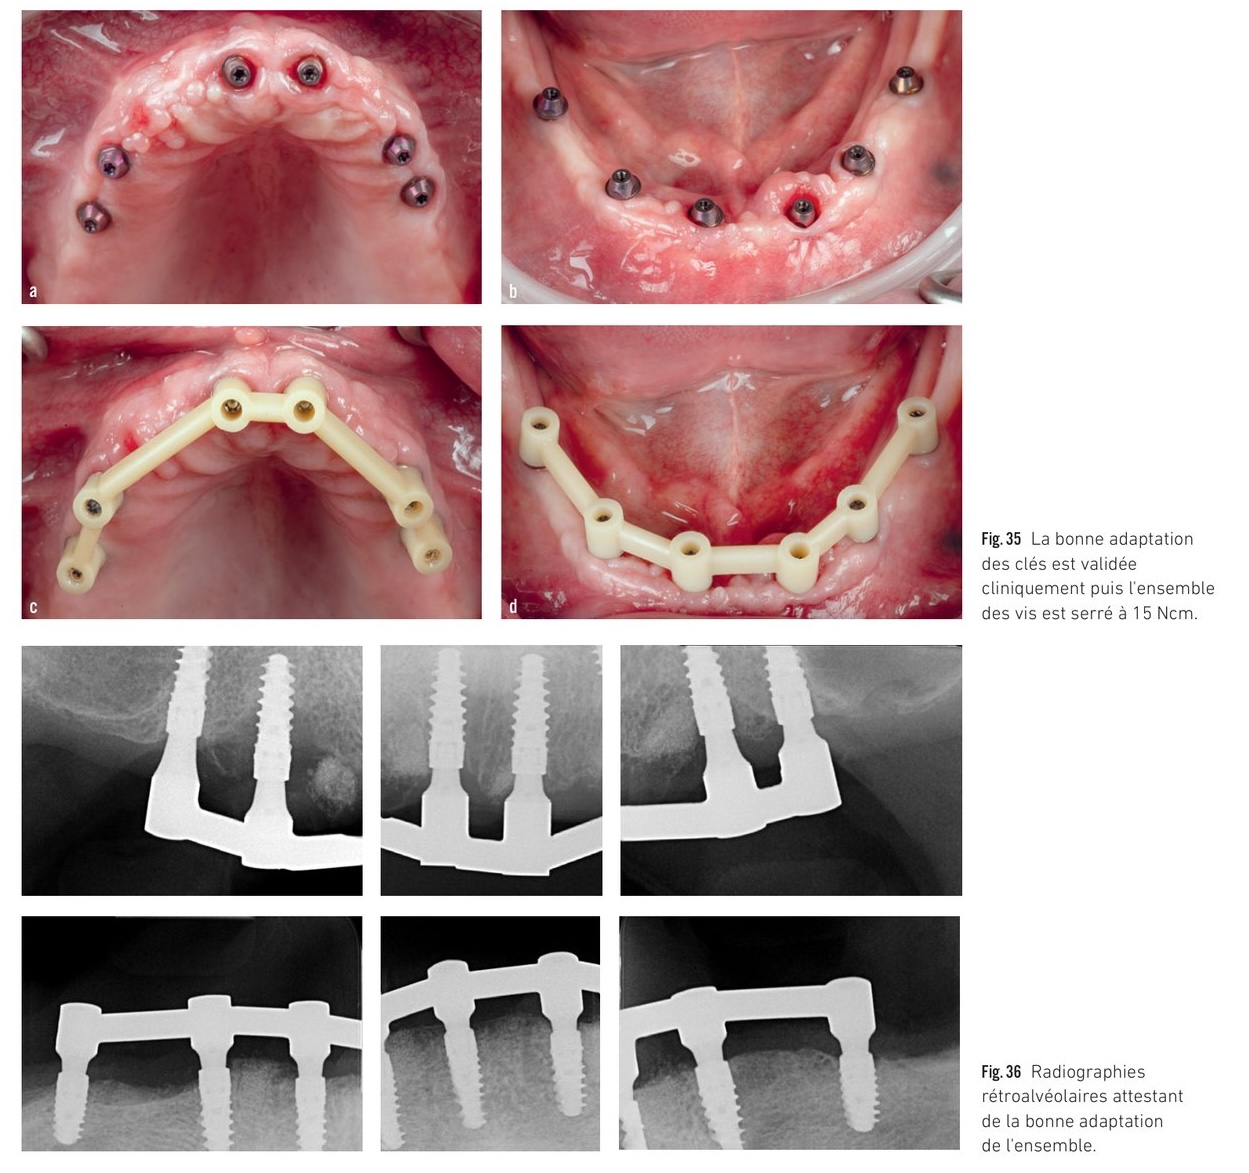

Validation clinique — clés de passivité, radiographies et prothèses zircone définitives